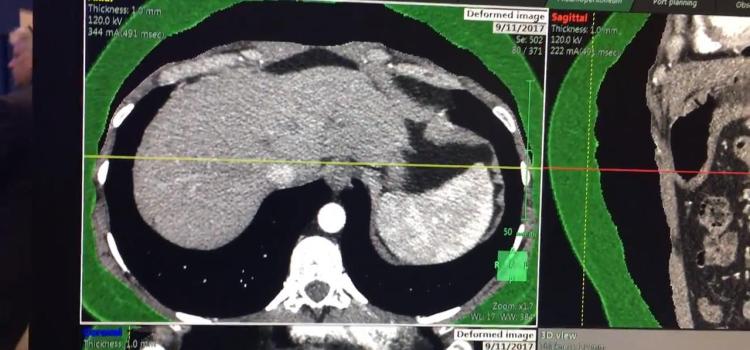

This is an example of a new endoscopic virtual peritoneal inflation tool on the patient's computed tomography (CT) ...

This is an example of a new endoscopic 3-D imaging simulator created from a patient's computed tomography (CT) scan ...